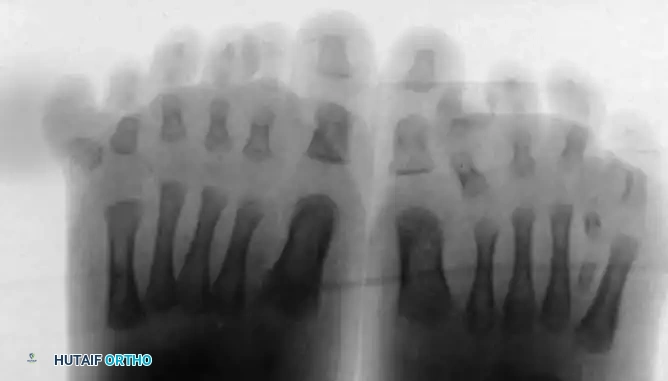

Bilateral polydactyly in a 6-month-old infant. Note the widening of the forefoot and the postaxial location of the supernumerary digits, which will inevitably complicate standard shoe wear.